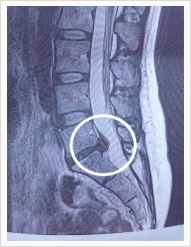

2年ぶりのMRI。当然ですが腰のヘルニアが消えてなくなっているわけでもなく、特に悪くなっているでもなく…もう本当にやっかいなヤツです結構大きいでしょ?ヤツとはもう20年以上の付き合いですが今回の腰痛、一時は歩けないほど辛かった・・・この痛みがなくなるのなら!と娘と元看護師の妹に支えられ恐怖のブロック注射を覚悟して病院へ行きました。がっ!!!いざ診察台に横たわりエビのように腰を丸められ、半分お尻を出した状態で看護師さん二人にガッチリ押さえ込まれると、恐怖で身体がガタガタ震えてくる・・・「杏仁豆腐さん、少し力抜きましょうよ…(苦笑)」とか言われてもヘタレな私、「あ…い…」と声まで震えております。「それじゃ、先に麻酔注射しますから~」と手際よく腰に何やらひんやりしたもの塗り始めた。多分消毒なんだろう。Σ(|||▽||| )怖い…。できることならこのまま気絶したい…塗るや否やブスッとやられ、痛っ!とか言う間もなく既に麻酔針刺さってはるここまで来ればヘタレな私でもまな板の上の鯉、もう好きなようにしてくださいですよ。数分後、皮膚に麻酔が効いたところでいよいよ0.9mmのブロック針登場!これでもかってほど固く目を瞑り、ぎゃ~っ!怖い!いやぁ~っ!え?( ̄_ ̄ i) 麻酔のせい?ちょっとゴリっていったけど…思ったほど痛くないし!助かった!薬液注入後、とりあえずお尻をしまってもらい30分ほどそのまま安静。そして・・・起き上がるのも悪戦苦闘してたのに、すんなり起きられる!すんなり立ち上がれる!普通に歩ける!嘘みたい!こんな当たり前のことがこんなに嬉しいだなんて…痛みがないってすごく幸せなことですよ。やっぱり健康第一ですね。

週末から持病の腰痛が暴れだし、歩くのもままならぬ状態でただいま静養中。 またしばらく自由のきかない生活を強いられそうです。 とにかく痛い...辛い...。(T_T) 出張以外で3日もめだかを見てないなんて... めだかに餌もあげられないなんて... 仕方なく母と娘にやってもらってます。 あぁ...ほんま辛い。 明日MRIの予約を入れてあるので行ってきます。 あの主治医、苦手なんだよなぁ〜(ー ー;)